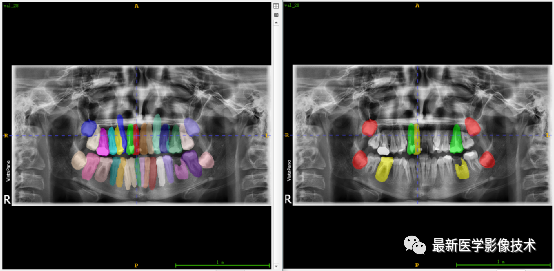

验证集牙齿分割计数和异常牙齿分割识别

左图是分割计数,右图是异常牙齿分割识别结果